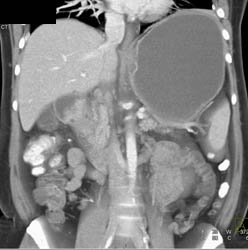

3D of Gastric Cancer